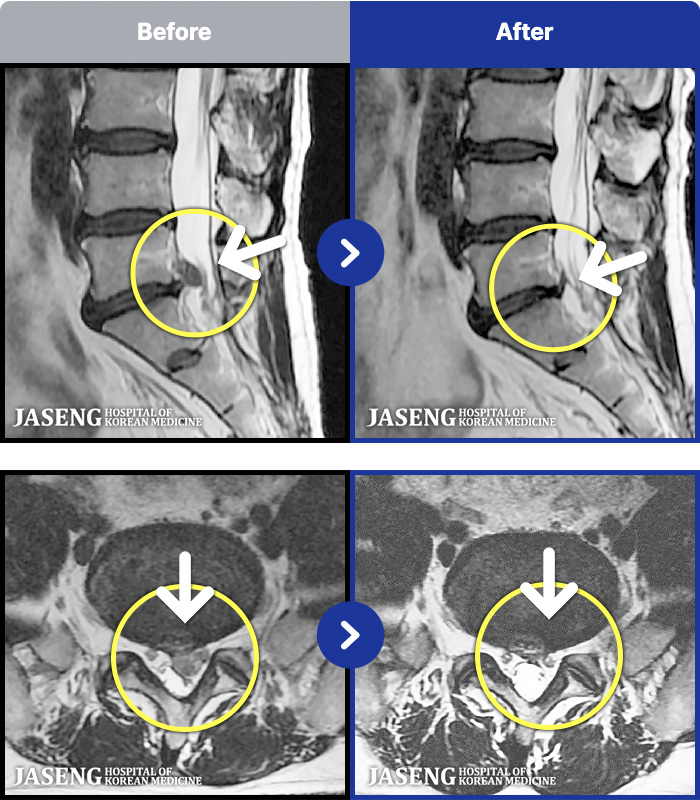

- MRI ġ

MRI ġ

1,240 MRI ũ ʸ Ȯϼ.